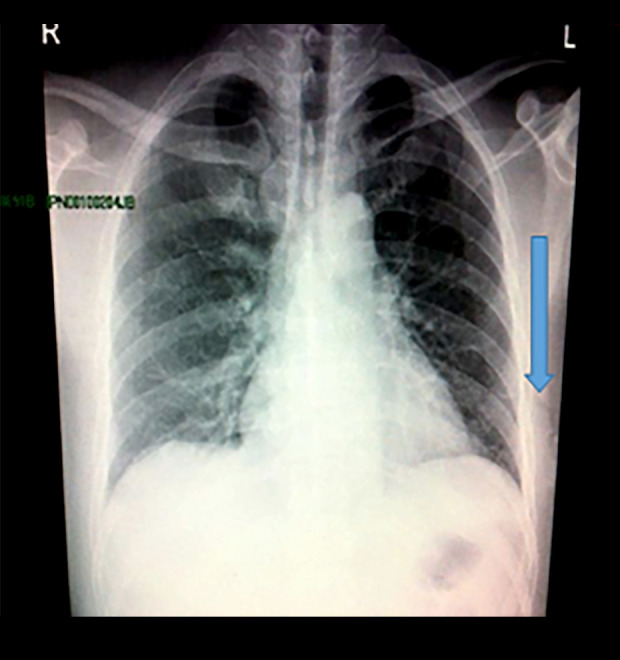

Figure 3.

Photomicrographs depict the histopathological features of necrotizing tissues affected by a necrotizing soft tissue infection. The images reveal extensive tissue necrosis, with large areas of cell death (green arrow). Additionally, there is evidence of acute suppurative inflammation (black arrow), characterized by the presence of numerous neutrophils and bacterial colonies, indicating a severe bacterial infection. These findings are consistent with a diagnosis of necrotizing soft tissue infection and highlight the aggressive nature of the inflammatory response.

Vital signs showed high-grade fever and tachycardia but normal blood pressure. Local examination revealed a tender, prominent erythematous swelling measuring approximately 15×12 cm occupying the left posterolateral area of the left chest between the fourth rib superiorly and eighth rib inferiorly, with frank pus discharge and foul odor (Figures 1, 2). The initial blood investigation revealed a white blood cell count of 17.5×109/L and a hemoglobin level of 14 g/dL. The chest X-ray showed suspicious gas in the soft tissues (Figure 3). An urgent contrast-enhanced computed tomography (CT) scan of his chest was performed. It showed subcutaneous, intramuscular abscess collection with gas formation between the muscles of the latissimus dorsi and serratus anterior measuring 13×6×11 cm, with suspicion of necrosis (Figures 4–6). The overlying ribs and lung parenchyma were intact.